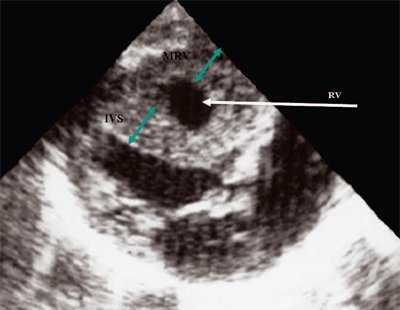

Нагрузка сопротивлением возникает при ситуации, когда выброс крови из желудочков сердца в магистральные сосуды затруднен на уровне полулунных клапанов (стеноз аорты и легочной артерии), подклапанного пространства (идиопатический гипертрофический субаортальный стеноз, подклапанный стеноз аорты или легочной артерии), на протяжении сосудистого русла (коарктация аорты) либо при значительном увеличении выходного сопротивления (синдром Эйзенменгера). В результате затруднения выброса крови резко возрастает напряжение миокарда соответствующего желудочка при относительно стабильном объеме крови, что служит проявлением систолической перегрузки сердца. При систолической перегрузке желудочков сердца независимо от нозологической формы порока полость желудочка, несущего основную нагрузку сопротивлением, умеренно увеличивается в размерах. В ответ на нагрузку сопротивлением на эхокардиограмме выявляется гипертрофия миокарда соответствующего желудочка, и чем больше сопротивление выбросу, тем резче выражена степень гипертрофии миокарда соответствующего желудочка и межжелудочковой перегородки (рис. 1) [3].

Рис. 1. Систолическая перегрузка правого желудочка. Поперечное сечение желудочков сердца при стенозе легочной артерии. Градиент давления правый желудочек - легочная артерия равен 200 мм рт.ст. Выраженная гипертрофия межжелудочковой перегородки и миокарда передней стенки правого желудочка.